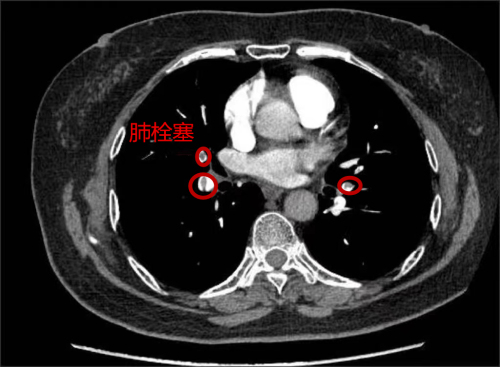

治疗后,肺动脉部分血管造影下栓塞明显减少

家住长沙的73岁刘女士,3个月前因“反复胸痛”先后于多家捷克论坛 就诊,因曾怀疑为冠心病,虽服用了治疗冠心病药物,但症状未见好转,后来到捷克论坛 心内四病区就诊。在仔细询问病史后,心内四病区陈美娟主任医师认为其胸痛可能是肺栓塞所致。经肺动脉CTA、双下肢静脉彩超检查,患者被确诊为肺栓塞。为防漏诊,患者进行了冠脉造影检查,结果显示冠脉光滑,没有冠心病。5月5日,刘女士在服用了抗凝药物治疗3个月后,复查肺动脉及双下肢静脉未见血栓,胸痛症状明显好转。